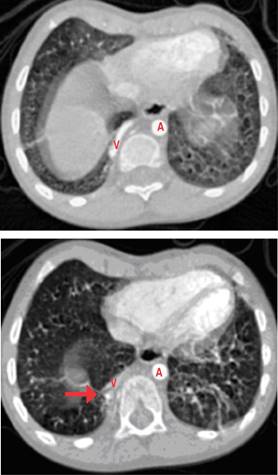

Estudios: difusión de monóxido de carbono (DLCO) 7.5 mL/min/mmHg (valor predicho 10.2), espirometría posbroncodilatador con una respuesta en volumen espiratorio forzado en el primer segundo (FEV1) del 16% y de más de 200 mL. La radiografía de tórax muestra un patrón atelectásico (Figura 1). Serie esofagogastroduodenal (SEGD) con presencia de reflujo grado III; en la angiotomografía de tórax (angio-TC) se observa una subclavia derecha aberrante (Figura 2), lo mismo que en la aorta descendente, también un vaso aberrante (Figuras 3 y 4).

Figura 3: Angiotomografía computarizada de tórax en la cual se observa la presencia de hipervascularidad pulmonar que genera una lesión sólida muy pequeña (flecha) y vaso nutricio (V) que nace de la aorta torácica descendente (A) y se localiza cerca del diafragma, de 4 mm de diámetro que se dirige a la región basal del pulmón derecho.